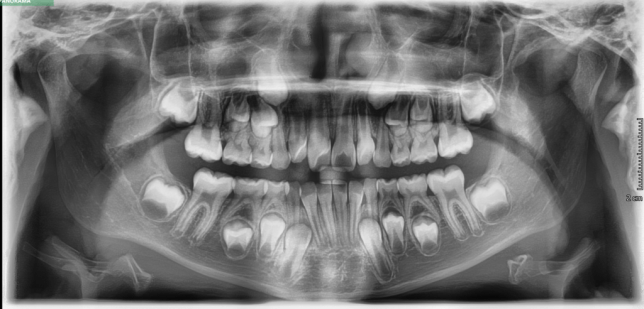

TREATMENT STARTED AT AGE : 9

- Myobrace K1 Medium

- Mixed Dentition

- Class 2 Div I

- Moderate